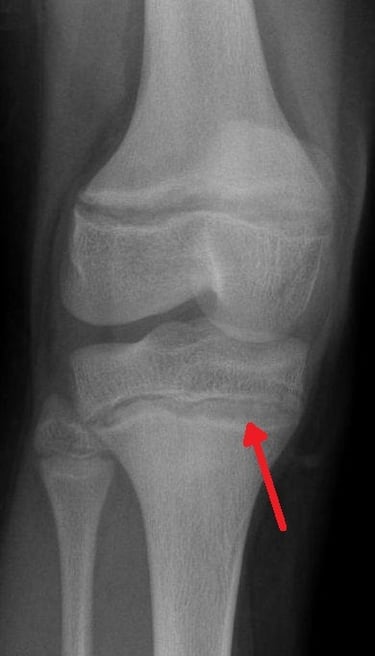

Periferik Yayma (Basofilik Noktalanma):

Mikroskopta eritrositlerin içinde "karabiber serpilmiş gibi" mavi noktalar görülür.

LR+ (Pozitif Olasılık Oranı): 15-20. (Yani bu bulgu varsa, kurşun zehirlenmesi olasılığı 20 kat artar. Çok güçlü bir kanıttır).